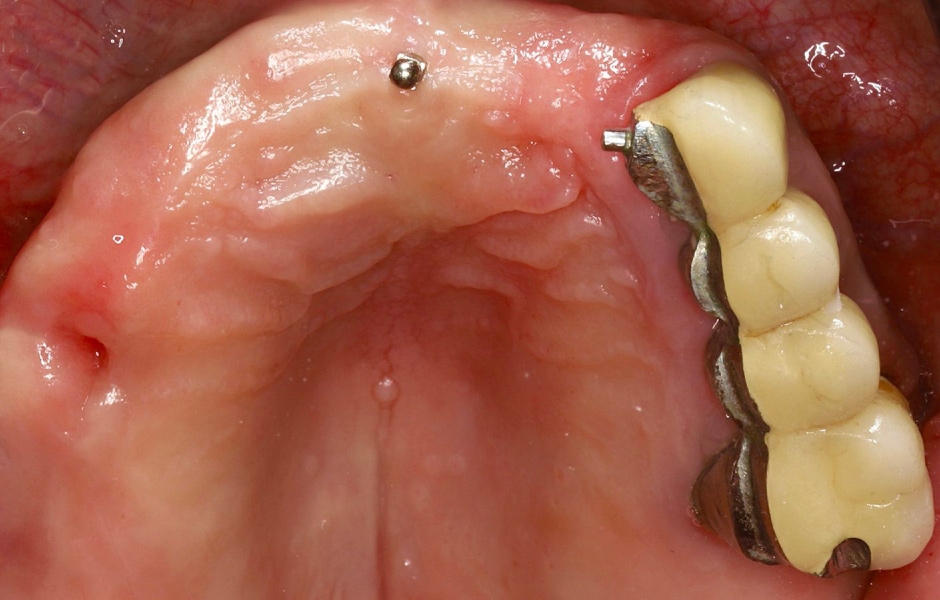

Při extraorální prohlídce nebyly zjištěny žádné významné abnormality. Pacient měl střední úroveň linie úsměvu (obr. 1–3). Po vyjmutí snímatelné náhrady byl odhalen můstek (obr. 4).

Intraorální vyšetření odhalilo starý můstek, který nahrazoval zuby 23 až 26 a zároveň sloužil ke kotvení částečné snímatelné náhrady s kovovou výztuží. Zuby 22 až 17 byly extrahovány již před delší dobou a alveolární hřeben v této oblasti byl zhojen. Nebyl přítomen plak ani zánět. Zuby vykazovaly mírnou až střední ztrátu attachmentu, ale nebyly pozorovány žádné parodontální léze nebo fraktury kořenů (obr. 5–8).

Obr. 3, 4

Obr. 5

Obr. 6

Obr. 7

Obr. 8